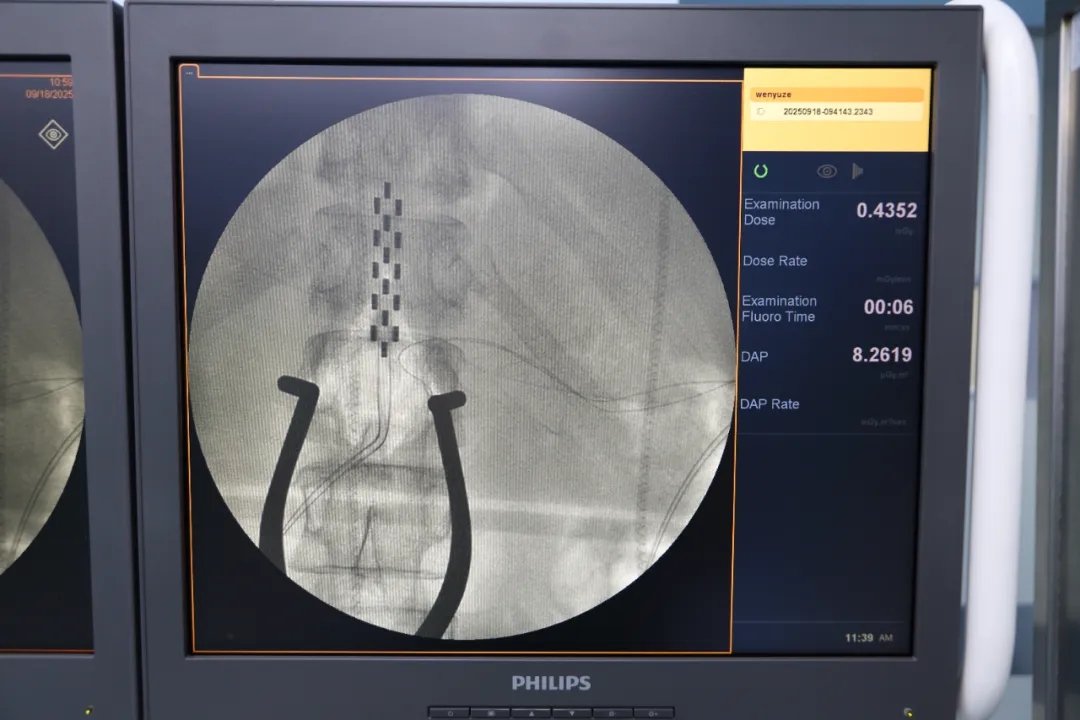

efccf60f2d47a6fded61fe242f38b340.jpg

(电极植入 示意图)

脊髓电刺激是一种通过植入电极向脊髓发送电信号的治疗方法,是一种神经调控技术,其基本原理是通过在脊髓硬膜外间隙植入电极并向电极传递低频电刺激。这些电刺激能够阻断疼痛信号通过脊髓向大脑的传递,使疼痛信号无法到达大脑皮层,从而达到缓解疼痛的目的;同时,电刺激还能调节神经元的活动,促进受损神经功能的恢复。